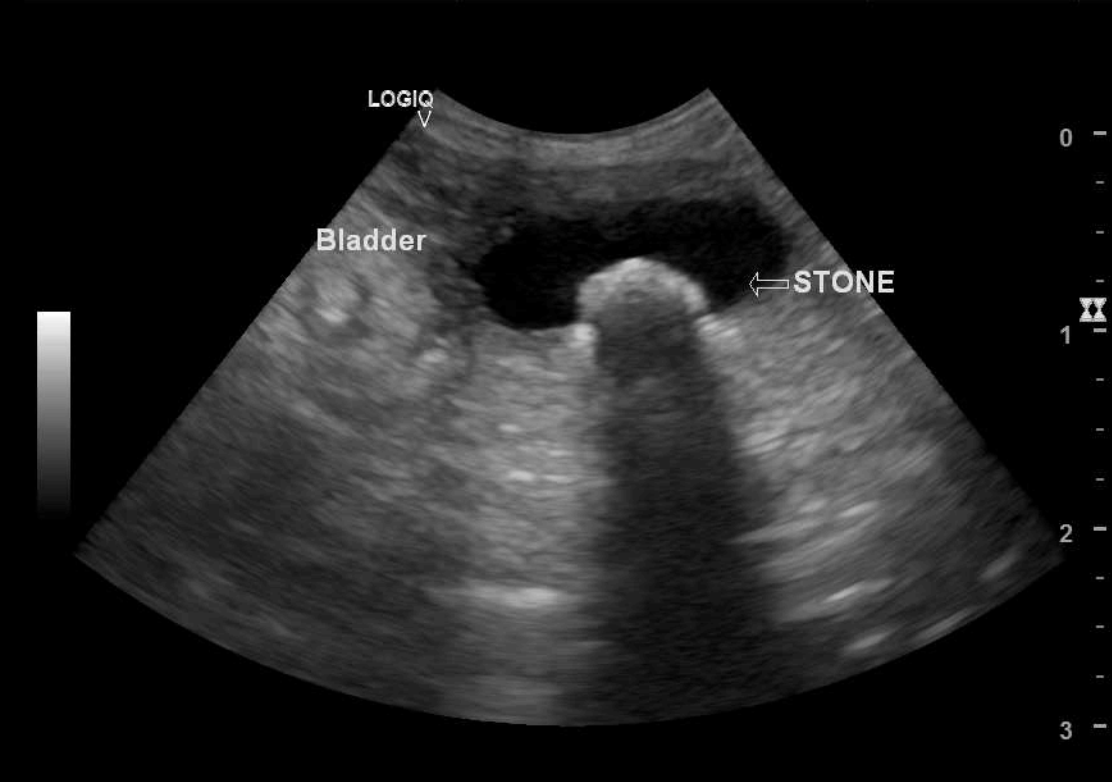

From www.semanticscholar.org

Figure 1 from Ultrasound Evaluation of the Urinary Bladder in Dogs Cat Bladder Ultrasound The present study confirms that ultrasonography is an efficient imaging method for examination of lower urinary tract, but radiography and contrast cystography are still. Evaluate the urinary bladder in long and short axes (figure 14). Therefore, do not let your cat urinate within three to six hours of the ultrasound procedure if possible. Ultrasound of the urinary bladder move the. Cat Bladder Ultrasound.